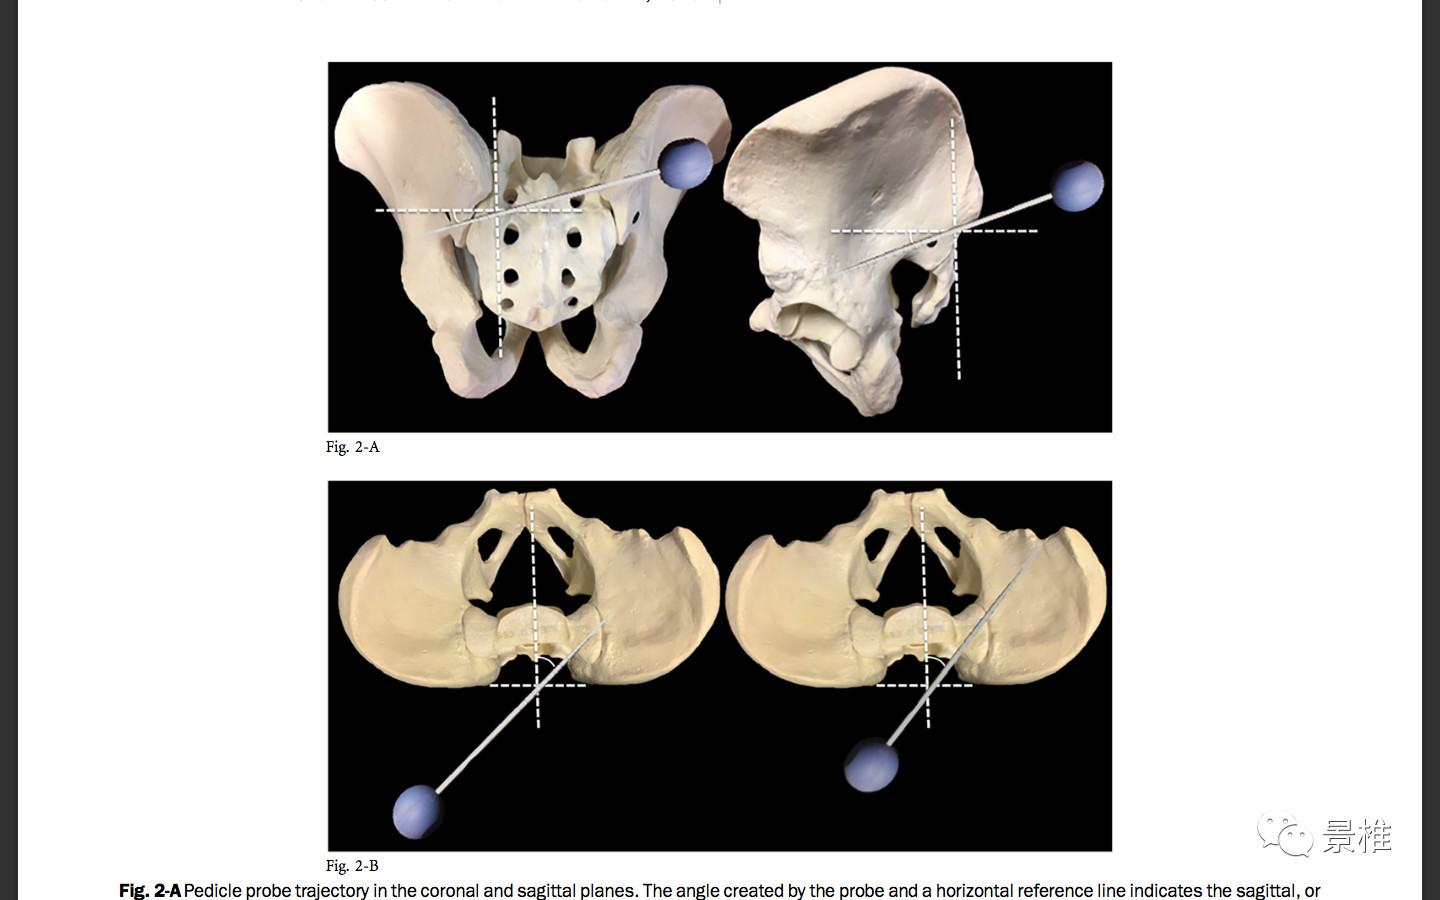

进针方向和水平面呈40°-50°夹角,和矢状面呈20°-30°夹角。

还有简便方法,那就是钉道朝向患者髂前下棘。俯卧位髂前下棘不好触及,摸大转子尖部也可以。开路锥指向同侧大转子尖端。